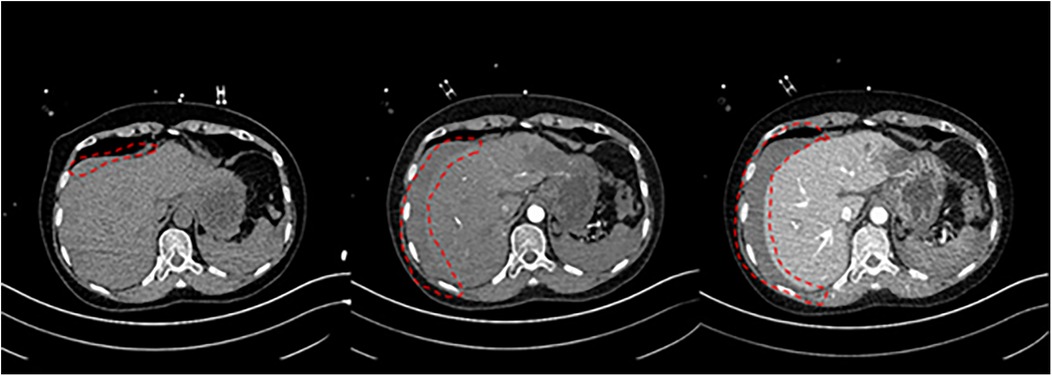

11 min after ECMO was started, the patient was transferred to the CT room. Abdominal CT and pulmonary artery CTA revealed the following findings: (1) Bilateral pulmonary artery embolism. (2) Exudation in the lower lobes of both lungs and multiple rib fractures on both sides. (3) Abnormalities in the right posterior lobe and left lateral lobe of the liver (Figures 1, 2).

Figure 1. Non-contrast CT of the abdomen, arterial phase, venous phase.

Three side-by-side MRI scans show cross-sections of the abdomen with a focus on a particular area outlined in red dashed lines. Each image highlights different sections or phases of the abdominal region, likely emphasizing changes or abnormalities.

Figure 3. Abdominal CT before discharge.